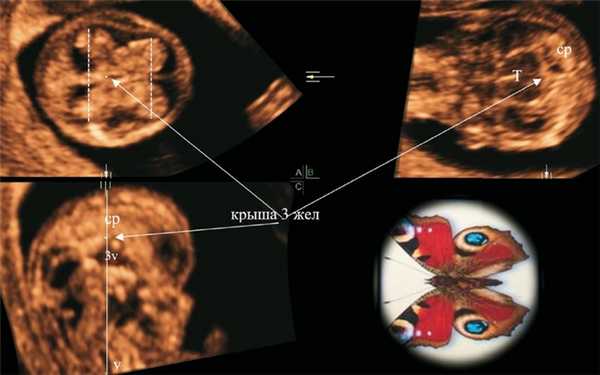

Согласно рекомендациям СС, T. Loureiro и соавт. [4] для стандартизации аксиальных срезов головного мозга проводилась коррекция изображения в трехмерном режиме для получения вертикального среднесагиттального среза (рис. 1). Ориентиром вертикальности при этом является нахождение на одной оси крыши III желудочка и I позвонка на плоскости С (см. рис. 1, плоскость С). При такой ориентации на аксиальном срезе на уровне крыши III желудочка СС боковых желудочков отражаются в виде «бабочки» (см. рис. 1, плоскость А). По аналогии с крыльями бабочки эта картина в норме предполагает превалирование расстояния между затылочными порциями СС над расстоянием между лобными порциями и характерное сужение (талия) по середине латерального контура СС.

Рис. 1. Ультразвуковая трехмерная реконструкция головного мозга плода в 12 нед + 2 дня. Референсная точка на уровне крыши III желудочка.

На плоскости С отображен вертикальный сагиттальный срез (крыша III желудочка и шейный отдел позвоночника на одной вертикальной оси), на плоскости А - аксиальный срез на уровне крыши III желудочка и признак «бабочки» сосудистых сплетений; ср - сосудистые сплетения боковых желудочков, v - позвоночник, 3v - III желудочек, Т - таламус.

На рис. 2 отображена нормальная картина головного мозга на трех стандартных уровнях аксиального среза у плода в 12 нед + 2 дня (копчико-теменной размер (КТР) 57,4 мм; бипариетальный размер (БПР) 19,5 мм), полученная в мультиплоскостном режиме.

Рис. 2. В режиме TUI отображена ультразвуковая картина трех стандартных аксиальных срезов головного мозга плода в 12 нед + 2 дня.

1 - трансталамический; 2 - на уровне крыши III желудочка; 3 - трансвентрикулярный. Эти срезы показывают, что картину «бабочки» можно получить только на уровне крыши III желудочка (3ж).

На этом рисунке видно, что СС имеют картину «бабочки» только на уровне крыши III желудочка. При подъеме уровня исследования выше на трансвентрикулярном срезе контур СС выравнивается, и они занимают практически все внутричерепное пространство.

Оценку СС в нашей работе мы проводили визуально (есть или нет правильная картина «бабочки») без проведения измерений параметров. На рис. 3 показан ряд нормальных картин «бабочки» СС боковых желудочков головного мозга плода, полученных при двухмерном ультразвуковом сканировании, в 12-13 нед беременности.

Рис. 3. Отображен ряд нормальных картин «бабочки» СС боковых желудочков головного мозга плода, полученных при двухмерном ультразвуковом сканировании, в 12-13 нед беременности.